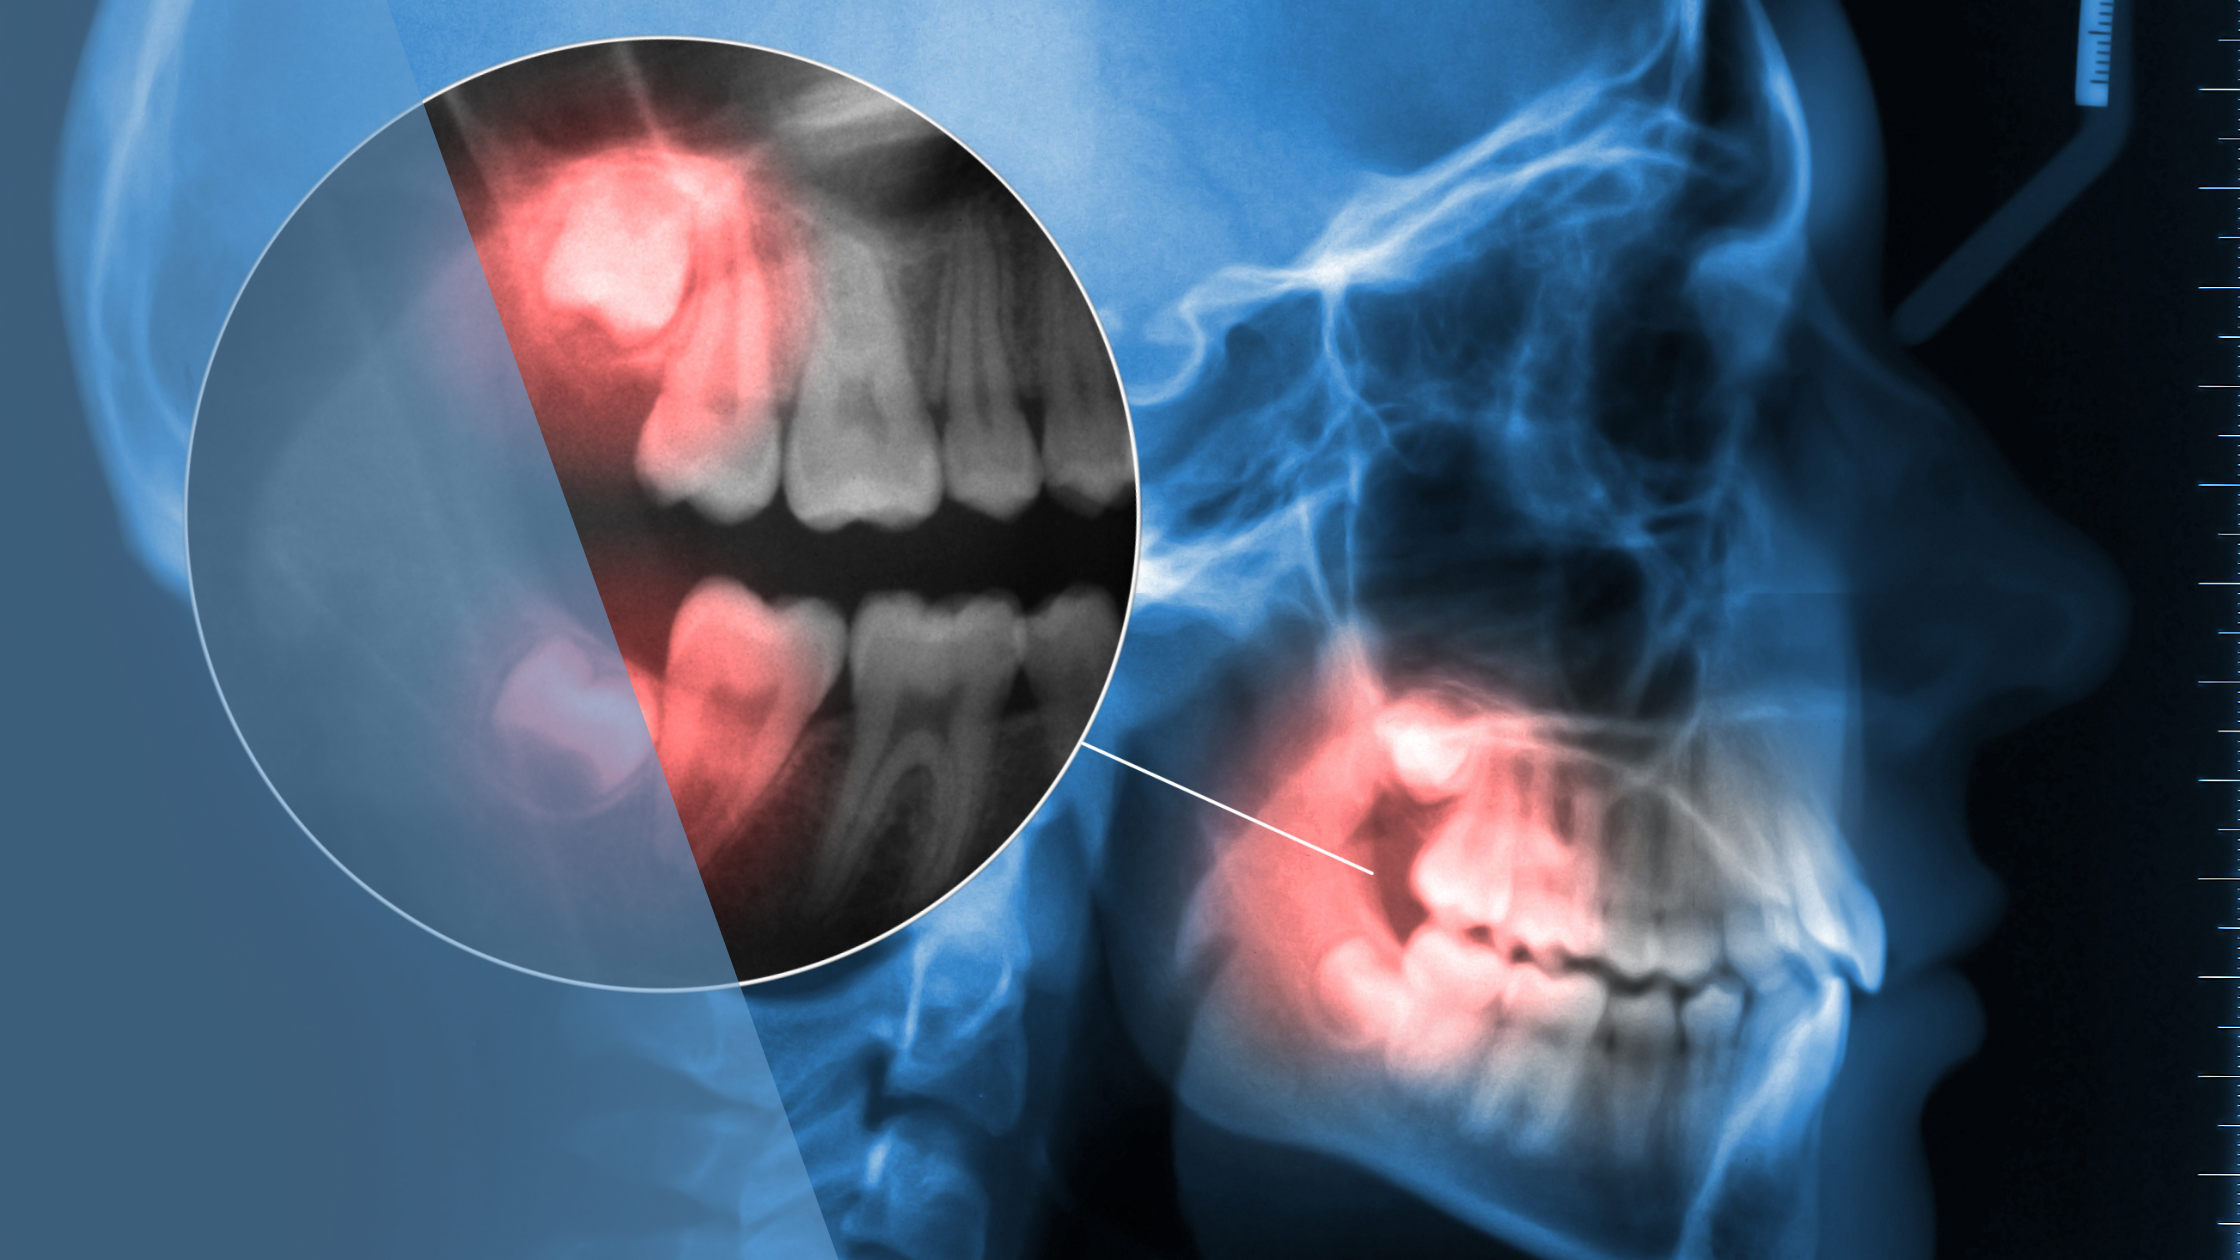

What makes teeth extractions surgical? Surgical extractions are required when teeth are impacted, partially erupted, or positioned at difficult angles.

Surgical wisdom teeth extractions involve:

- Incisions in the gum tissue

- Possible bone removal

- Tooth sectioning for easier removal

- Sutures to close the surgical site

Impacted Wisdom Teeth Extractions

How do impacted teeth affect recovery? Impacted wisdom teeth extractions are the most complex procedures and require the longest recovery periods.

A study published in the Journal of Oral and Maxillofacial Surgery found that patients with fully impacted teeth extractions experienced an average recovery time of 7-10 days before returning to normal activities. This is significantly longer than the 2-3 days needed for simple extractions.